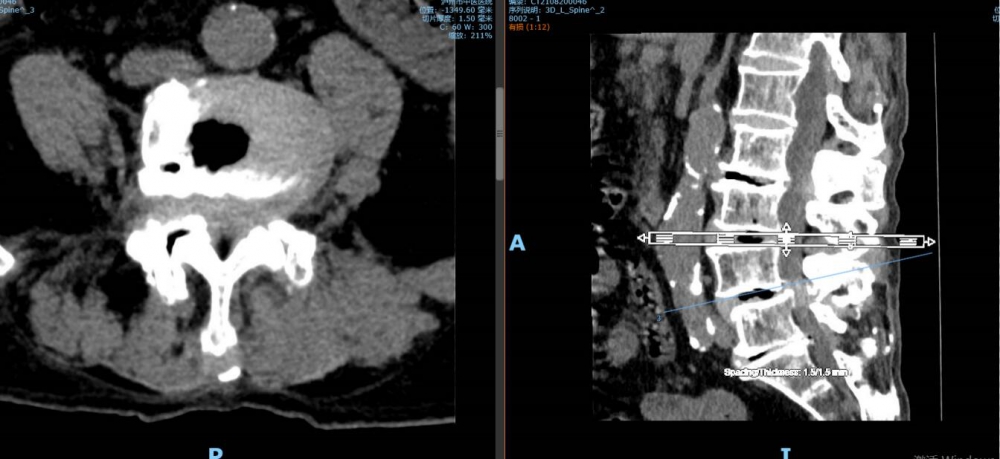

“我‘考试’去了,你们不要担心”。8月27日上午8点,92岁高龄的李谨行老人被推进了泸州市中医医院的手术室,进手术室前,老人乐观地宽慰着儿女们。此番,医生将为老人进行骨科手术,若手术成功,老人将结束几乎瘫痪在床的日子;老人同时还患有腰椎管狭窄症等17种疾病,这样的情形下,无论是对老人的身体还是医生而...